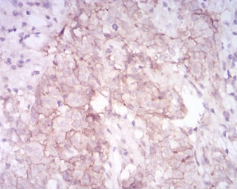

MMP14 Mouse Monoclonal antibody[61D1]

Proteins of the matrix metalloproteinase (MMP) family are involved in the breakdown of extracellular matrix in normal physiological processes, such as embryonic development, reproduction, and tissue remodeling, as well as in disease processes, such as arthritis and metastasis. Most MMP's are secreted as inactive proproteins which are activated when cleaved by extracellular proteinases. However, the protein encoded by this gene is a member of the membrane-type MMP (MT-MMP) subfamily; each member of this subfamily contains a potential transmembrane domain suggesting that these proteins are expressed at the cell surface rather than secreted. This protein activates MMP2 protein, and this activity may be involved in tumor invasion.

Immunogen:    Purified recombinant fragment of human MMP14 (AA: 112-246) expressed in E. Coli.

IHC    1/200 - 1/1000